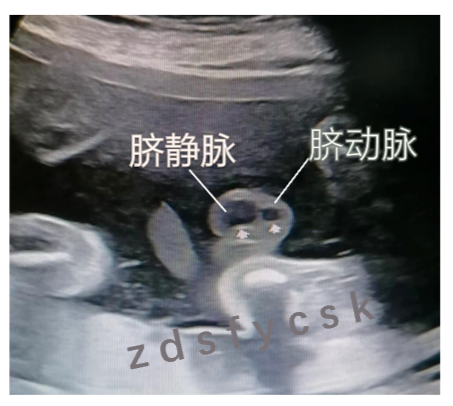

脐带连接着胎儿和母体,是母体和胎儿血液循环的纽带。正常脐带内有两条脐动脉和一条脐静脉。当脐带内只有一条脐动脉和一条脐静脉的时候,称为单脐动脉。

单脐动脉